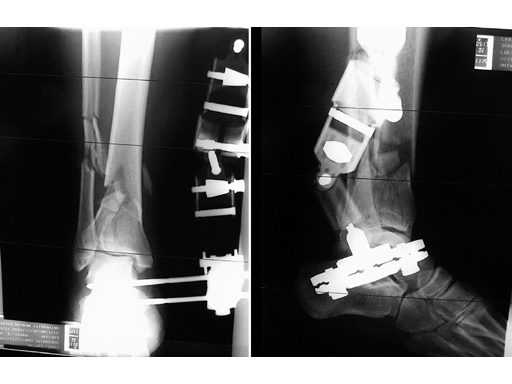

The Adjustable Large External Fixator is indicated for fractures of the tibia and femur, joint bridges, and osteotomies. Its pivoting T-clamp and convergent pin slots allow for fixation of shaft fractures as well as of tibial pilon and plateau fractures. The radiolucent, pre-assembled fixator is applied to the bone using a minimum of four Schanz screws through two pin clamps. The body of the Adjustable Large External Fixator is of radiolucent fibre-reinforced PEEK. The overall length ranges from 295 mm to 354 mm depending on clamps and distractor travel. The pin placement for the innermost pins ranges from 132 mm to 215 mm. It features two spring-loaded 6-position pin clamps. ML/AP angulation, torsion of 45 in each direction and gross (45 mm) and fine (35 mm) distraction/compression. The Adjustable Large External Fixator is equipped with new Reduction Handles, a 5 mm Combination T-Wrench, and a 9 mm Combination Wrench.

51-year-old man